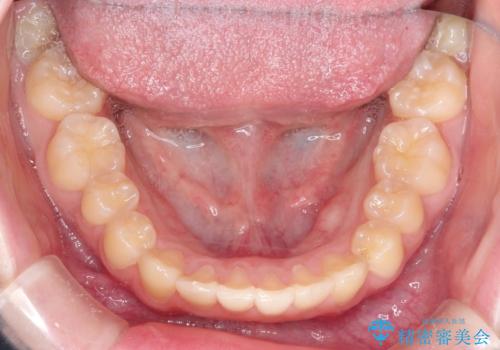

- 上下の前歯のガタガタを治したいとのことで来院されました。

上下の歯と歯の間をわずかに削り、並べる計画としました。